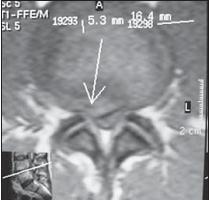

На МРТ № 15 наблюдается двухсторонняя экстрафораминальная грыжа межпозвонкового диска (расположенная за межпозвонковыми отверстиями) На МРТ № 16 наблюдается медиолатеральная протрузия и вентральная грыжа межпозвонкового диска